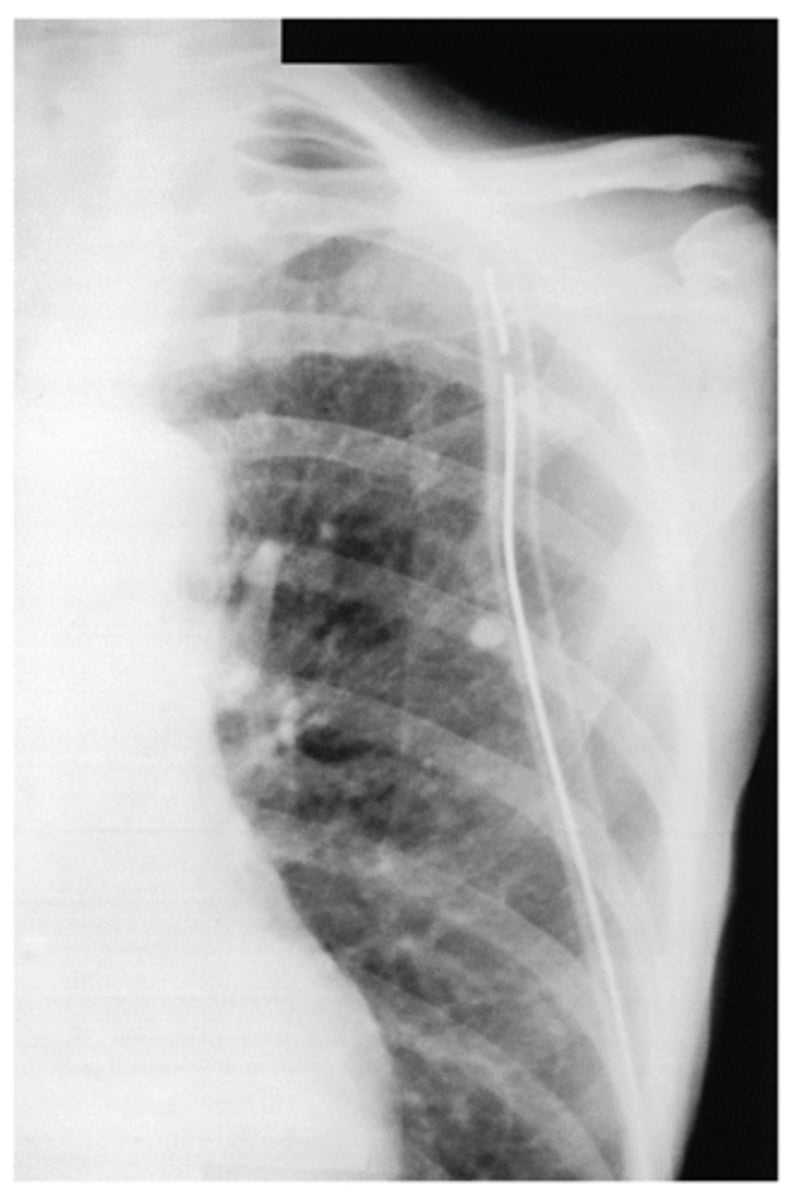

CXR of tracheal intubation with ETT

What is going on in this CXR?

Chest tube (tip of tube should be posterior and near apex of lung for drainage)

What is goin going on in this CXR?